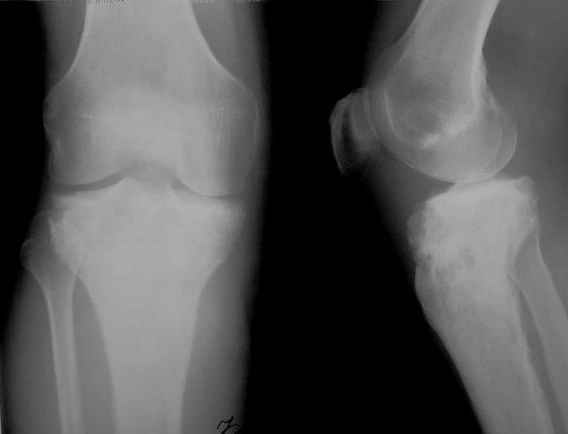

Ещё одно клиническое наблюдение - лимфома кости, до и после ПХТ и лучевой терапии.

Примите мои извенения, если я Вас чем-либо обидел. Никакого пренебрежения, просто хотел поделиться наблюдением, а главное, результатом консервативного (ПХТ и лучевая терапия) лечения.